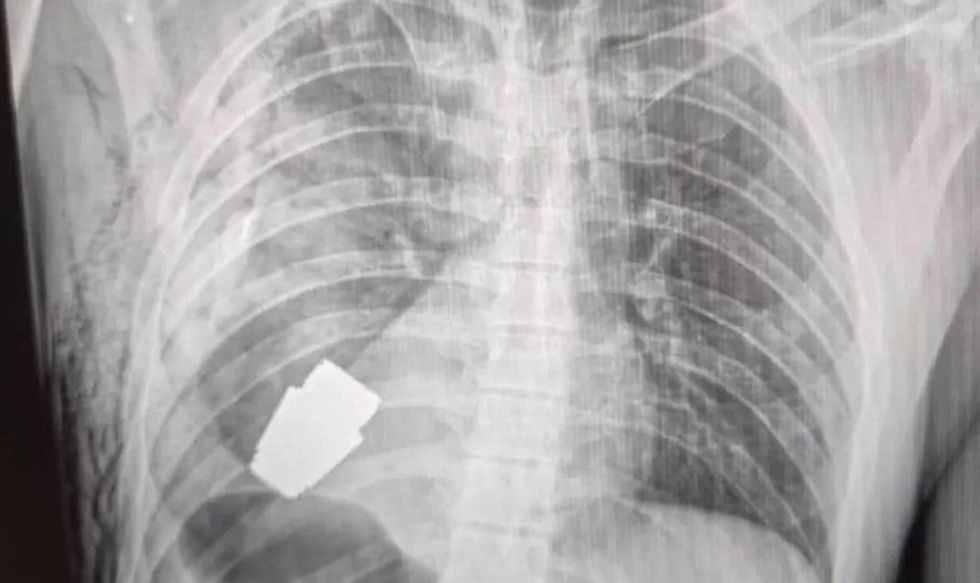

Një granatë e pashpërthyer është hequr nga gjoksi i një ushtari ukrainas.

Sipas mediave të huaja, përcjell Telegrafi, imazhet para dhe pas të publikuara nga shërbimi mjekësor i forcave të armatosura të Ukrainës tregojnë pajisjen afër zemrës së ushtarakut dhe një tjetër të kirurgut që mban pajisjen e lyer me gjak.

Ndërkohë është thënë se pajisja ishte një granatë VOG - një copë municionesh 4 cm e gjatë, e cila gjuhet nga një granatëhedhës dhe mund të udhëtojë rreth 400 metra, dhe është projektuar të shpërthejë pak mbi tokë.